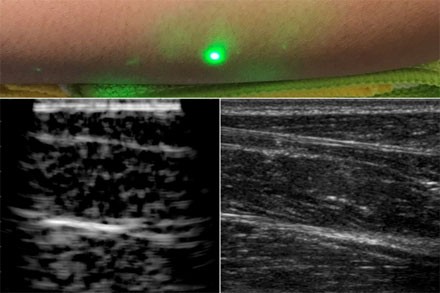

據(jù)外媒報(bào)道,12月24日,麻省理工學(xué)院的工程師設(shè)計(jì)了一種常規(guī)超聲成像的替代方法,這種方法不需要與身體接觸,可用于無(wú)法忍受探針進(jìn)入身體的患者,如嬰兒、燒傷患者或皮膚敏感的患者。在掃描志愿者前臂的試驗(yàn)中,研究人員能夠觀察到皮膚以下約5厘米處常見的組織特征,如肌肉、脂肪和骨骼。這些圖像與傳統(tǒng)的超聲波相當(dāng),是使用聚焦在半米外的遠(yuǎn)程激光產(chǎn)生的。由于聲波比光傳播到體內(nèi)的距離要長(zhǎng),因此研究人員首先研究如何在皮膚表面將激光束的光轉(zhuǎn)換成聲波,以便在體內(nèi)成像更深。該團(tuán)隊(duì)選擇了1550 nm激光器,該波長(zhǎng)很容易被水吸收,并且對(duì)眼睛和皮膚都是安全的,有很大的安全邊際。由于皮膚主要由水組成,因此研究小組認(rèn)為皮膚應(yīng)有效吸收該波長(zhǎng),并且它會(huì)隨著反應(yīng)而升溫和膨脹。當(dāng)它振蕩回到正常狀態(tài)時(shí),可以預(yù)期皮膚會(huì)產(chǎn)生通過(guò)身體傳播的聲波。研究人員用一個(gè)1550nm的脈沖激光產(chǎn)生聲波,用另一個(gè)調(diào)諧到相同波長(zhǎng)的連續(xù)激光遠(yuǎn)程探測(cè)反射聲波,驗(yàn)證了這一想法。第二個(gè)激光是一個(gè)運(yùn)動(dòng)探測(cè)器,它測(cè)量了聲波從肌肉、脂肪和其他組織反射到皮膚表面所引起的振動(dòng)。反射聲波產(chǎn)生的皮膚表面運(yùn)動(dòng)引起激光頻率的可測(cè)量變化,通過(guò)對(duì)全身激光進(jìn)行機(jī)械掃描,研究人員能夠在不同的位置獲取數(shù)據(jù),并生成該區(qū)域的圖像。一種新的超聲波技術(shù)利用激光在皮膚下產(chǎn)生圖像,而不像傳統(tǒng)的超聲波探頭那樣與皮膚接觸。新的激光超聲技術(shù)被用來(lái)產(chǎn)生一個(gè)人類前臂的圖像(左),這也是使用常規(guī)超聲成像(右)。由X.Zhang等人提供。研究人員首先利用這一新的裝置,將金屬物體嵌入一個(gè)類似皮膚含水量的明膠模具中進(jìn)行成像。他們用商業(yè)超聲探頭對(duì)同一明膠成像,發(fā)現(xiàn)兩幅圖像相似。然后,他們對(duì)切除的動(dòng)物組織(在本例中是豬皮)進(jìn)行成像,發(fā)現(xiàn)激光超聲可以區(qū)分細(xì)微的特征,如肌肉、脂肪和骨骼之間的界限。最后,研究小組利用麻省理工學(xué)院人類實(shí)驗(yàn)委員會(huì)批準(zhǔn)的方案,在人類身上進(jìn)行了第一次激光超聲實(shí)驗(yàn)。在掃描了幾名健康志愿者的前臂...